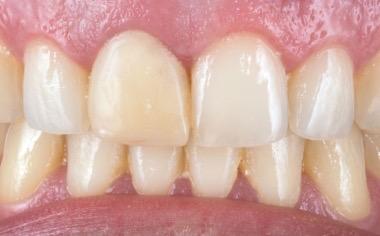

Restoring anterior teeth with large defects using composite seems to be quite challenging. With high-performance materials at hand and a systematic layering concept in mind, however, it is possible to produce highly aesthetic results in a reproducible way. The clinical case below is used to illustrate a dual-shade layering technique with CLEARFIL MAJESTY™ ES-2 Premium, a composite system with pre-defined colour combinations.

The patient, a young male, was unhappy with the appearance of his maxillary anterior teeth. Several years ago, his central incisors had been restored with composite. These existing restorations had defective and heavily discoloured margins, while their shade did not match the adjacent natural tooth structure. The maxillary lateral incisors were peg-shaped (microdontia). Economic considerations and the desire to save as much natural tooth structure as possible made the team decide to restore all four maxillary incisors with composite. CLEARFIL MAJESTY™ ES-2 Premium became the material of choice as it eliminates the need for complicated shade combination formulas and supports predictable outcomes.

We decided to restore the central incisors first and then focus on the lateral incisors. The tooth shade was determined using the VITA™ classical A1-D4 shade guide, while composite buttons were applied to the teeth to verify the determined shade combination. In order to simplify the restoration procedure, a palatal silicon index was produced before removing the existing restorations.

An adhesive (CLEARFIL™ Universal Bond Quick) was applied after selective etching of the enamel to achieve a strong bond. With the aid of the silicon index, it was easy to create the palatal shells of the restorations with CLEARFIL MAJESTY™ ES-2 Premium in the shade A3E (enamel), which matches the determined tooth shade A3. The dentin core was built up with the same composite in the recommended shade A3D (dentin), mamelons were modelled and some CLEARFIL MAJESTY™ ES-2 Premium in the shade WD added for the incisal halo, while some individual effects (like enamel cracks) were imitated with brown stain. The build-up was finalized in the interproximal and labial areas with composite in the shade A3E. Between the central incisors, a wedge was used to retract the papilla and facilitate the designing of the interproximal contact area. The finished and pre-polished restorations already had a natural appearance.

Fig. 6 Situation after finalization of the central incisor restorations with composite in the enamel opacity.

Fig. 4 Light-cured palatal shells made of CLEARFIL MAJESTY™ ES-2 Premium in the shade A3E.

Fig. 7 Central incisor restorations after finishing and initial polishing.

Fig. 5 Build-up of the dentin core with mamelons individualized with the shade WD and brown stain.

Fig. 8 Build-up of the left lateral incisor.

Two different opacities, a single shade combination and some bleached shade plus stain for special effects – in the present patient case, a simple formula allowed us to create lifelike anterior restorations. With one enamel and one dentin paste used, it is possible to simply rebuild the natural anatomy without the risk of ending up with a bulky core that – once reduced – will lose its special optical structure. It is also easy to control the thickness of the final enamel layer with its huge impact on the light-optical properties of the whole restoration. For most patients and teeth with a simple or medium-to-complex internal colour structure, the selected concept is very well suited and will lead to pleasing outcomes.